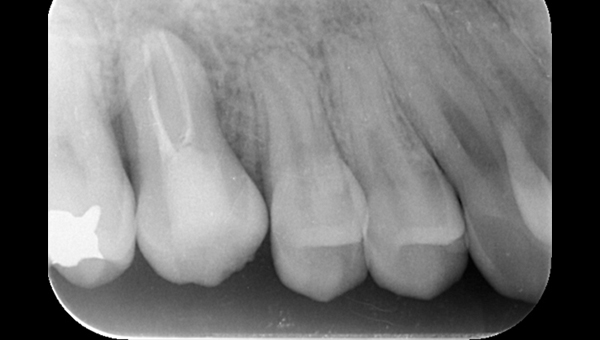

2022.7.9 経過観察後

口腔内写真

レントゲン写真

根管治療後3ヶ月です。根のまわりの骨がやや白くなってきているのがわかります。だんだん骨の添加がみられている証拠になります。

ここまで治癒していればかぶせ物をかぶせても問題ないと判断しました。

2022.8.13 クラウンセット

2022.10.16 予後経過

1年後 2023.3 予後経過

移植した歯はしっかり機能しており、問題なく使用できているとのことである。

最後のレントゲンでは、骨がしっかり添加され、周囲組織となんら変色ない状態にまでなっていることがわかる。